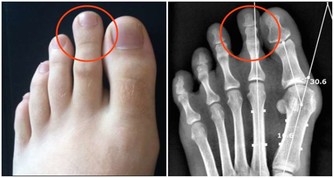

2、鼻腔結構異常引起鼻塞

鼻腔結構異常在世界範圍內是比較常見的,有先天的,也有後天創傷造成的,這種異常也會引起鼻塞。